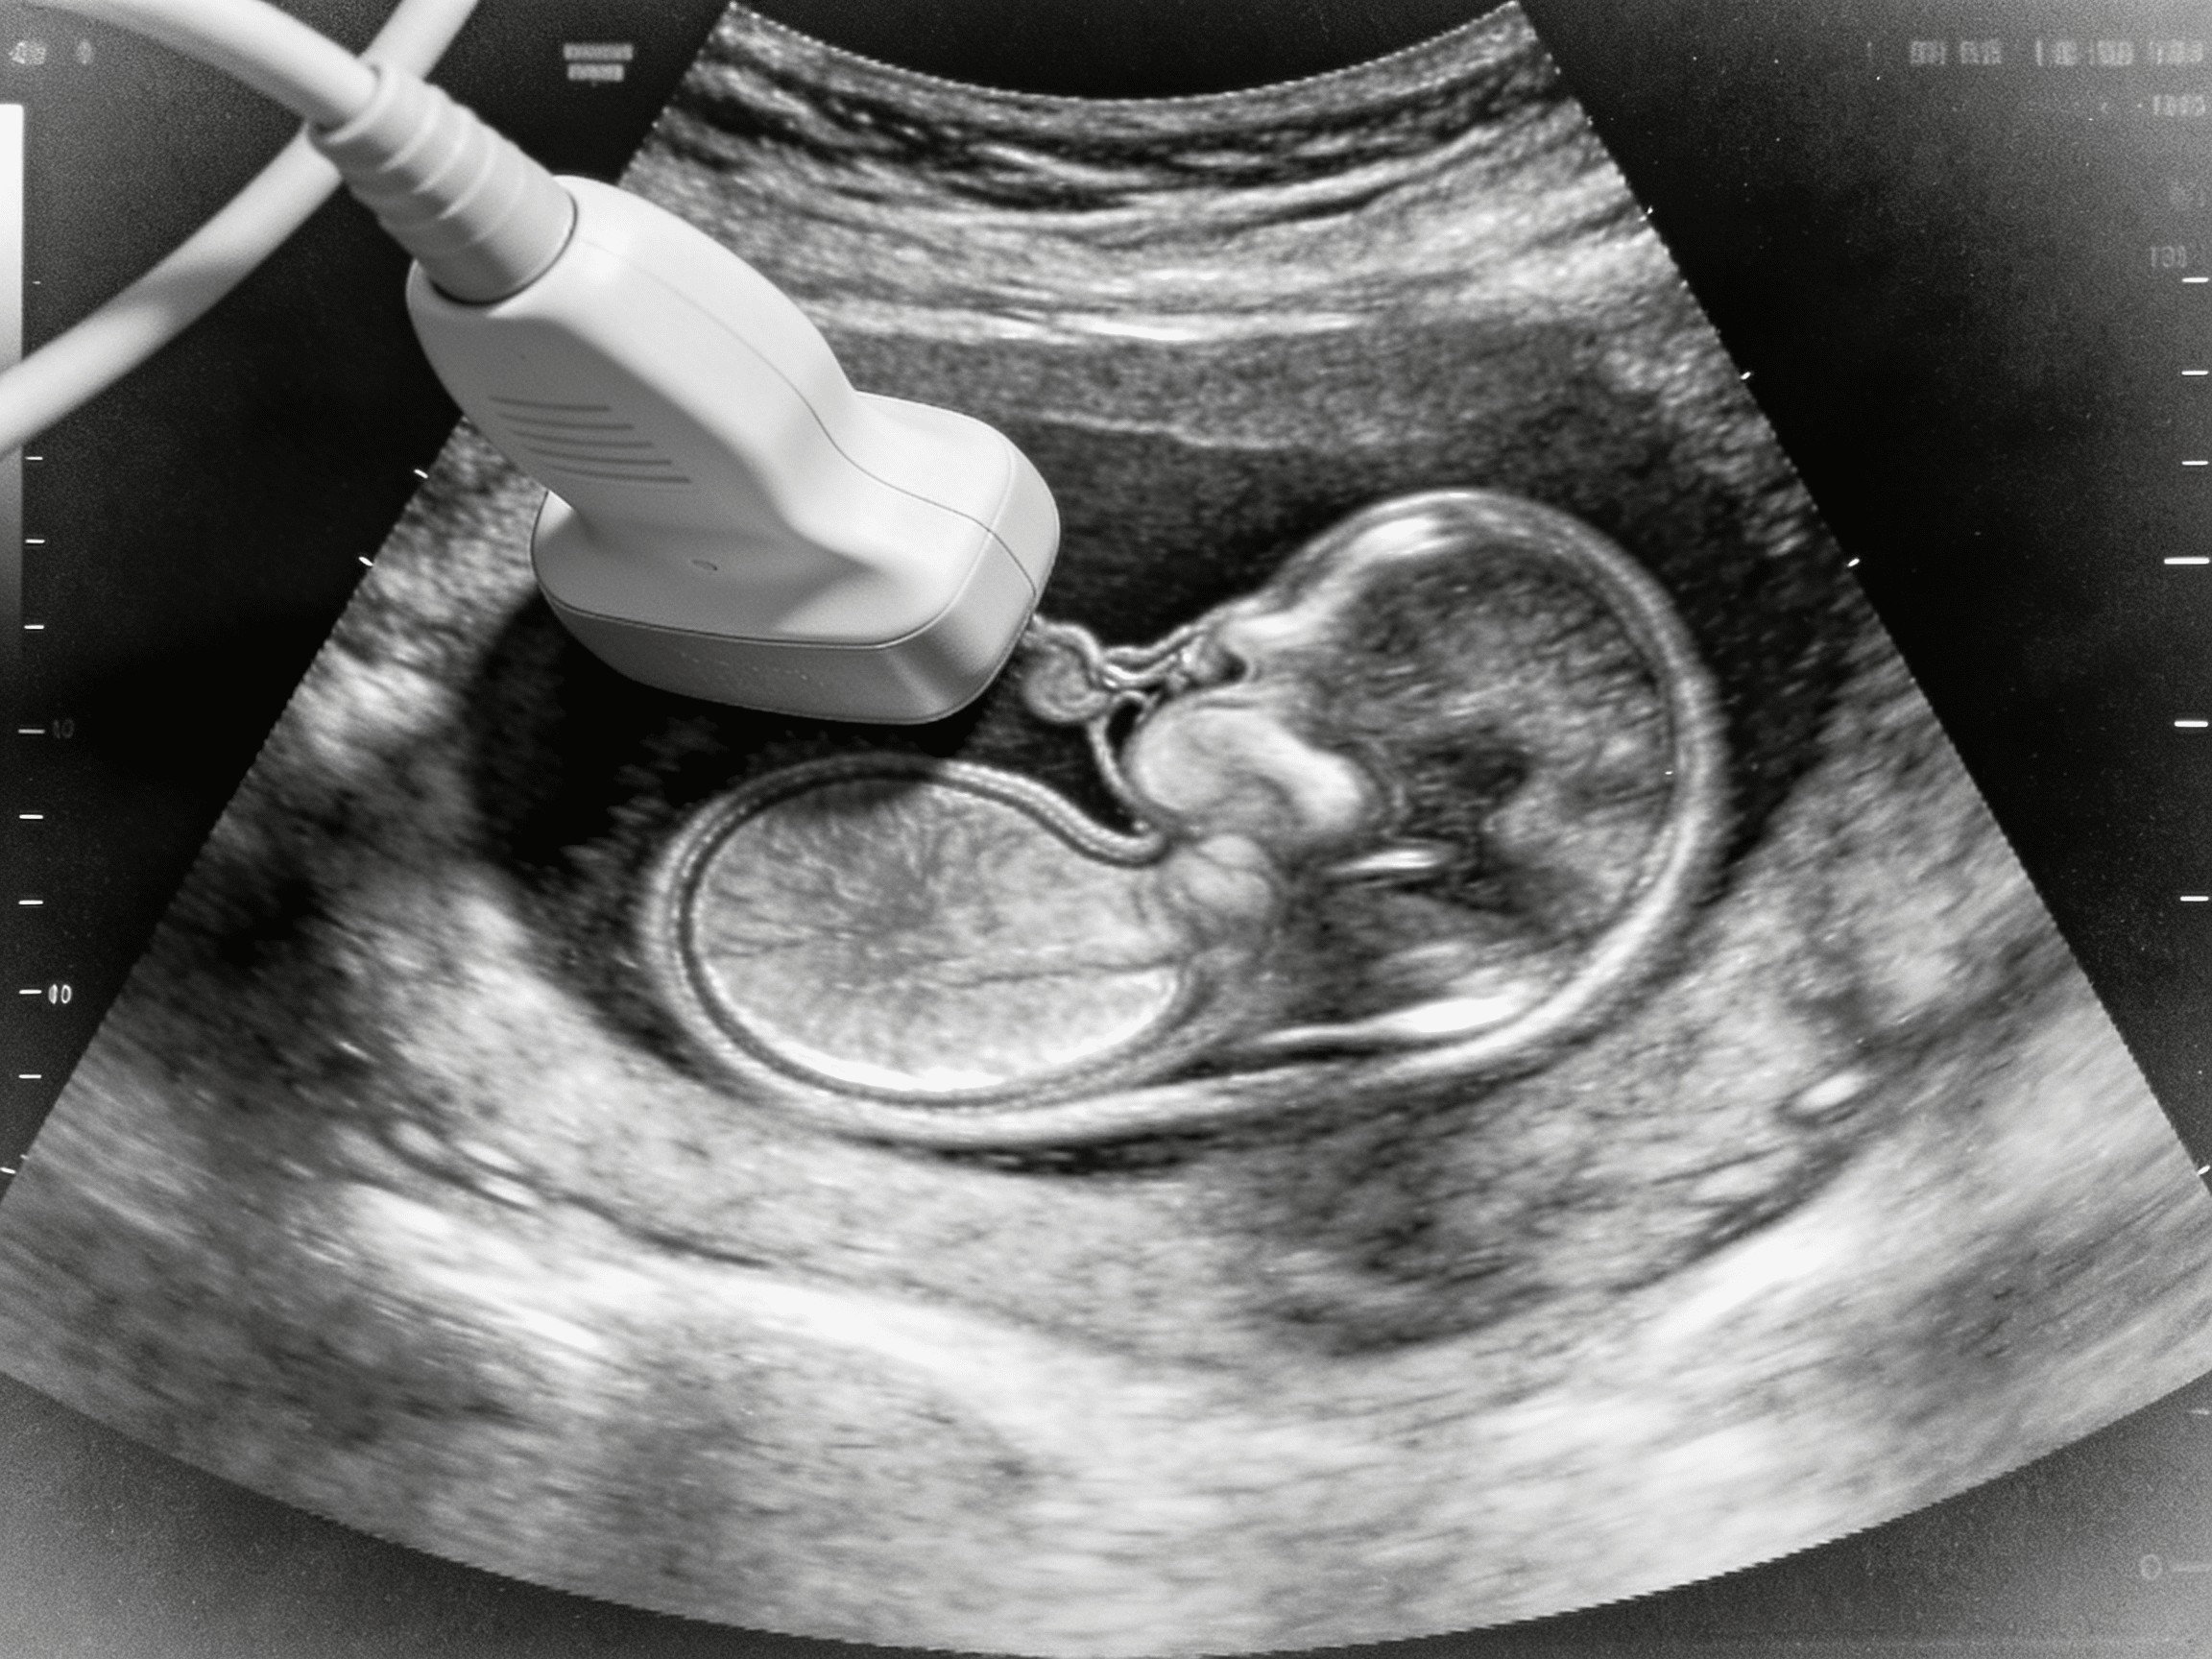

Emergency physician performing transvaginal ultrasound at Priority ER

Board-certified emergency physicians providing immediate transvaginal ultrasound and gynecological evaluation